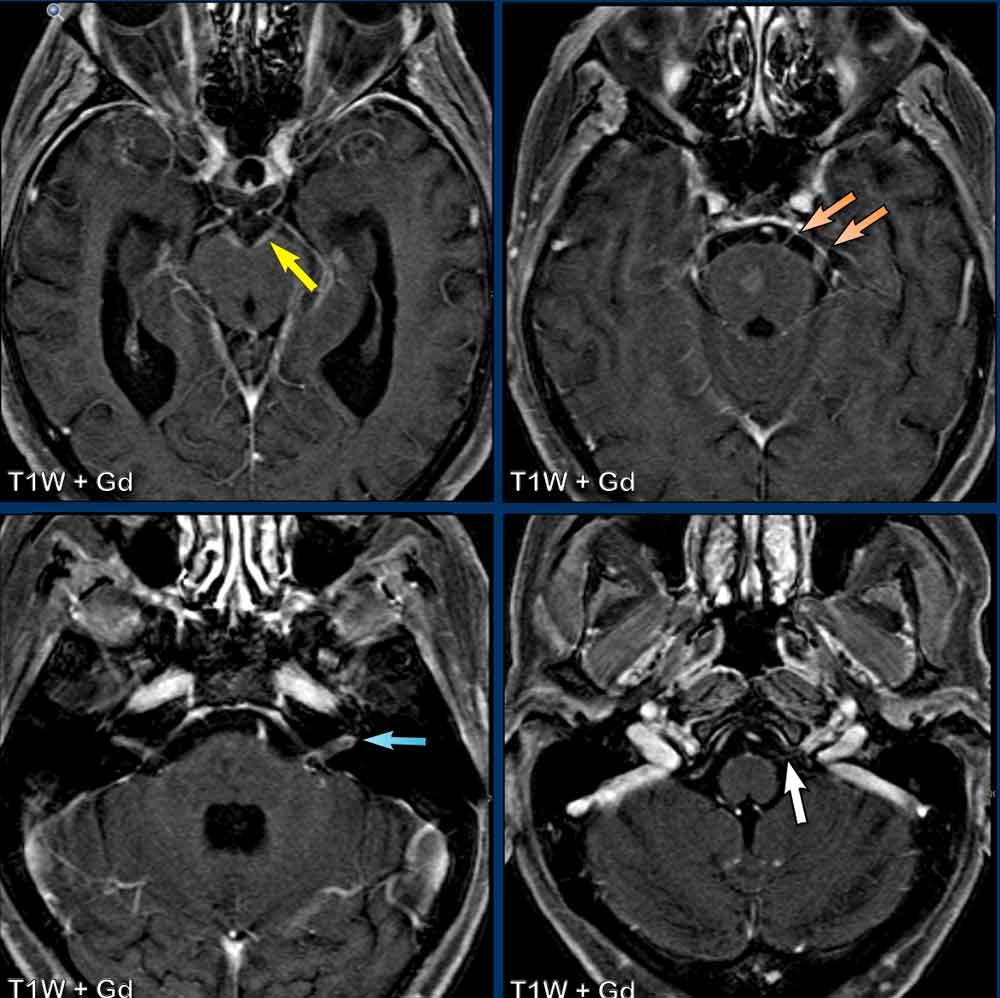

Các hình ảnh này thuộc về một nam bệnh nhân 62 tuổi nhập viện vì liệt dây thần kinh vận nhãn (dây III) bên trái.

Hình ảnh

Chuỗi xung FLAIR cho thấy tăng tín hiệu lan rộng ở cầu não và trung não.

Có hình ảnh ngấm thuốc dạng chấm và dạng tuyến tính.

Khi kết hợp các điểm ngấm thuốc ở các mức độ khác nhau, có thể nhận thấy đây thực chất là một phần của kiểu ngấm thuốc tuyến tính hoặc quanh mạch máu.

Chẩn đoán phân biệt:

- Các hình ảnh này gợi ý CLIPPERS, mặc dù đáp ứng với corticosteroid chỉ có thể được đánh giá sau khi điều trị.

- Hội chứng hủy myelin thẩm thấu vùng cầu não thường có vị trí trung tâm hơn.

- Thiếu máu cục bộ biểu hiện khuếch tán hạn chế và không có ngấm thuốc quanh mạch máu.

Tiếp tục xem hình ảnh sau điều trị của bệnh nhân này…

Bệnh nhân này được điều trị bằng corticosteroid và hình ảnh ngấm thuốc quanh mạch máu không còn được ghi nhận trên phim chụp theo dõi.

Tiếp tục xem các lát cắt sagittal…

Trên chuỗi xung T2W lát cắt sagittal, vùng tăng tín hiệu (mũi tên vàng) cũng đã biến mất trên hình ảnh theo dõi (mũi tên xanh lá).